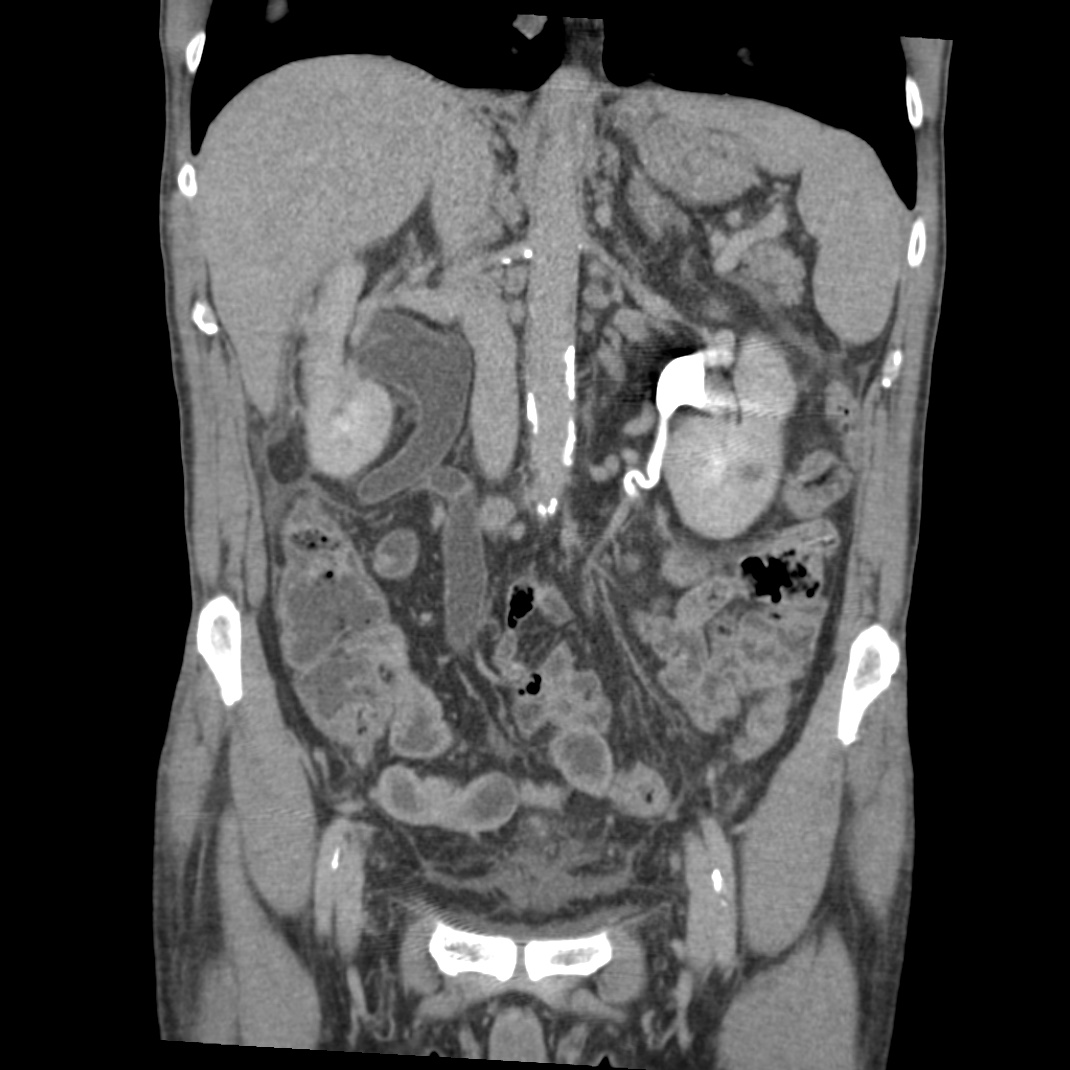

Se realiza nueva TC bifásico abdominopélvio y Uro TC.

- Paciente con numerosas recidivas por Cá vejiga.

- Ha desarrollado un tumor metacrónico en pelvis renal derecha, también responsable de la hidroureteronefrosis.

- Mala evolución radiológica del proceso a expensas de metástasis pulmonares y hepáticas.